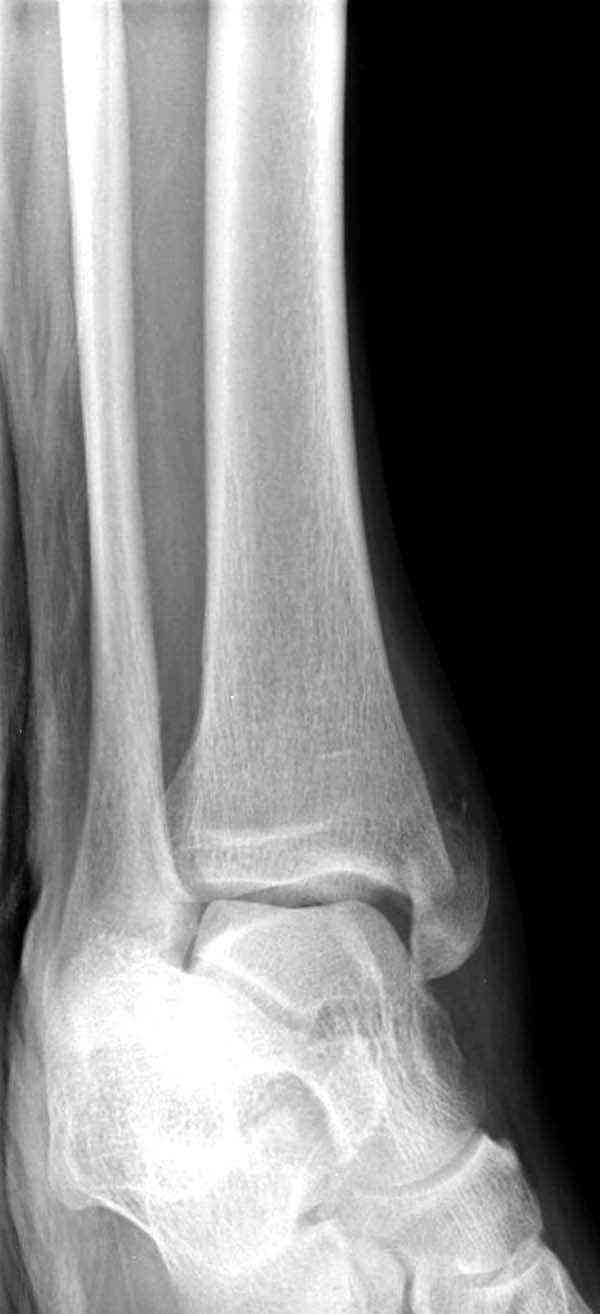

Нет первичных снимков, перелом очень низкий и под большим сомнением диагноз разрыва синдесмоза. Медиальная сторона отрепонирована на "хорошо" и, по-видимому, прорезание проволоки произошло во время операции. Без снимков трудно судить о высоте малоберцовой, а лодыжка находится в варусе. Лагирование получилось, но возле тонких шурупов передне-задний шуруп выглядит немного тяжеловато.

Коллеги правы, что при рутинных переломах достаточным бывает обычные снимки с мортизом. А стрессовые рентгенограммы могут уточнить, есть ли разрыв синдесмоза.

Здесь несколько частных случаев: перелом голеностопа со сравнительными снимками и разрыв синдесмоза, а также медиальная Hook пластина.